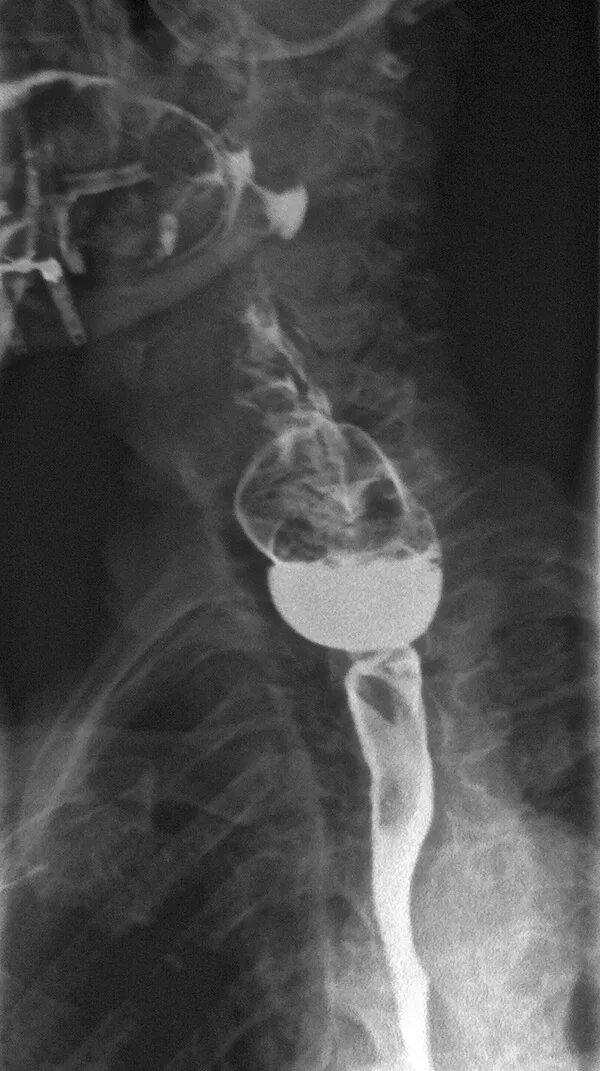

Дивертикул трахеи